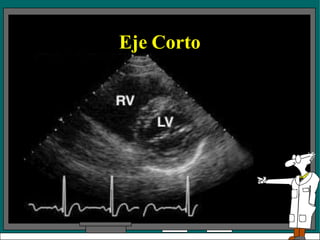

Eje corto

• Hay 4 posiciones del transductor para los

exámenes en eje corto del VI.

• El plano l da una vista de la punta del

corazón

• La posición 2 es una vista a nivel de los

músculos papilares.

• El plano 3 esta a nivel de la válvula mitral.

• El plano cuatro da una vista a nivel de la

válvula aórtica.